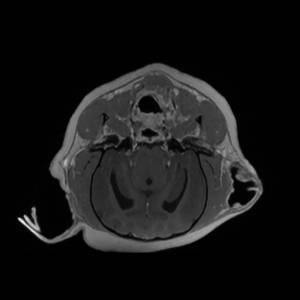

Main Gallery

Playing with a photo gallery function. It is possible to have multiple galleries, each within a namespace.